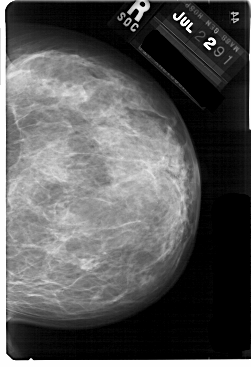

A_1757_1.RIGHT_MLO

RIGHT_MLO LINES 5491 PIXELS_PER_LINE 4021 BITS_PER_PIXEL 12 RESOLUTION 43.5 NON_OVERLAY